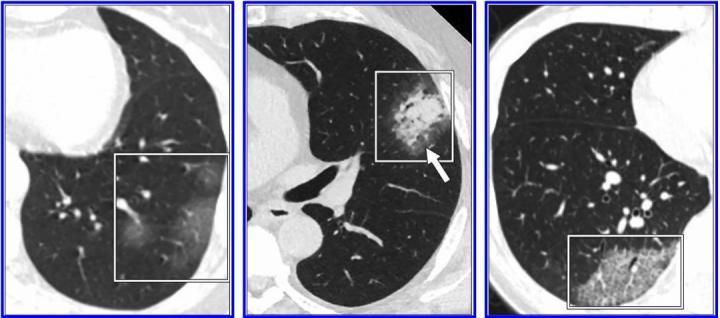

Figure 1 Imaging Changes In Severe Covid 19 Pneumonia Springerlink

link.springer.com